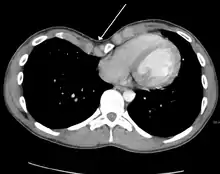

تم تطوير العديد من المقاييس لتحديد درجة التشوه في جدار الصدر. العديد من هذه المقاييس تعتمد على مدى التغير في المسافة بين عظمة القص و العمود الفقري. أحد هذه المقاييس هو مقياس بيكر الذي يحدد مدى درجة شدّة التشوه بناءً على النسبة بين قطر الدائرة لجسم الفقرة الأقرب للناتئ الرهابي والمسافة بين التقاطع الرهابي وأقرب جسم فقرة.[12] مؤخراً تم استخدام مقياس هولر الذي يعتمد على استخدام قياسات الأشعة المقطعية. المقياس الذي يفوق 3.25 يعتبر شديد.[13] مقياس هولر هو النسبة بين المسافة المقطعية لداخل القفص الصدري، وهي أقصر مسافة بين الفقرات وعظمة القص.[14]

التصوير الشعاعي للصدر يساعد في تشخيص المرض بشكل كبير. كما ان التصوير الشعاعي في الصدر المقعر يُظهر بعض الغموض في بعض الأحيان في الرئة اليمنى لأنها أكثر تعرضاً لاستنشاق للأجسام الغريبة (مثلما يحدث في الاتهاب الرؤوي).[15] كما تشير بعض الدراسات على استخدام مؤشر هالر ويحسب بناءا على التصوير الشعاعي بدلاً من الفحص بالأشعة المقطعية للأشخاص الذين لديهم تعارضات مع الأشعة المقطعية.[16]

علاج الصدر المقعر من الممكن أن يتضمن علاج شديد التوغل أو علاج طفيف التوغل أو علاج يتضمنهم جميعاً. يجب عمل أكثر من نوع من الفحوصات قبل البدء بالعلاج. ومن هذه الفحوصات التصوير المقطعي، اختبارفحص وظائف الرئه، والفحوصات القلبيه ( مثل التسمع لنبضات القلب و جهاز تخطيط كهربائيه القلب). وبعد أخذ التصوير المقطعي للصدر يتم استخراج نتيجة وحسابات مؤشر هالر. و يتم احتساب مؤشر هالر المريض عن طريق الحصول على النسبة من القطر المستعرض (المسافة الأفقية من داخل القفص الصدري) والقطر الأمامي الخلفي (أقصر مسافة بين الفقرات والقص).[17] إذا كان مؤشر هالر أكثر من 3.25 تعتبر الحالة المرضية جداً خطيرة. مؤشر هالر الطبيعي هو 2.5 .[18][19] الفحوصات القلبية والرئوية جميعها تستخدم للتعرف على القدرة الرؤية وللفحص عن اي خلل موجود بالقلب عن طريق التسمع إلى أصوات القلب.